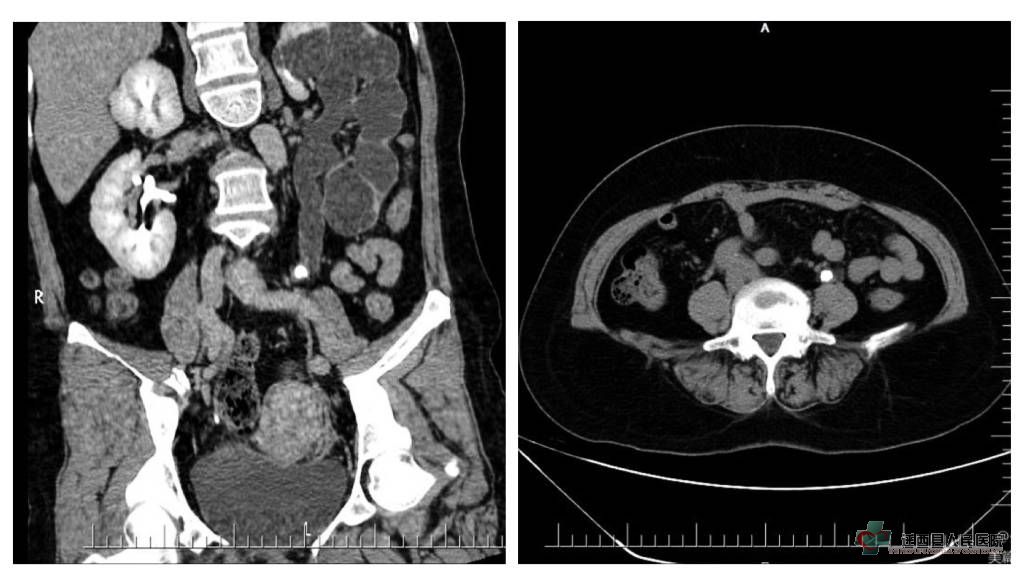

近日,泌尿外科收治了一名左侧输尿管上段结石患者,患者入院前已发现左侧输尿管结石2个月余,结石直径近1.5cm,且未采取积极治疗,按惯例,应行输尿管镜碎石治疗,但完善检查后发现患者病情并非想象的那样简单,泌尿系CT显示左侧输尿管结石伴有左肾重度积水,梗阻段输尿管及左肾皮质及其薄弱(如下图)。